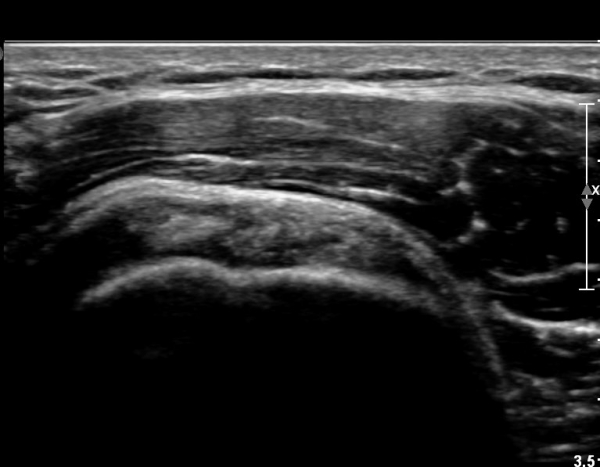

ŽÃËÀÚ¸¦ Á¶±Ý ´õ ¸»´Ü¹æÇâ(caudal)À¸·Î À̵¿ÇÏ´Ï ÆÄ¿­ÀÌ ´õ¿í ¶Ñ·ÈÇÏ´Ù(»çÁø 2, 3).